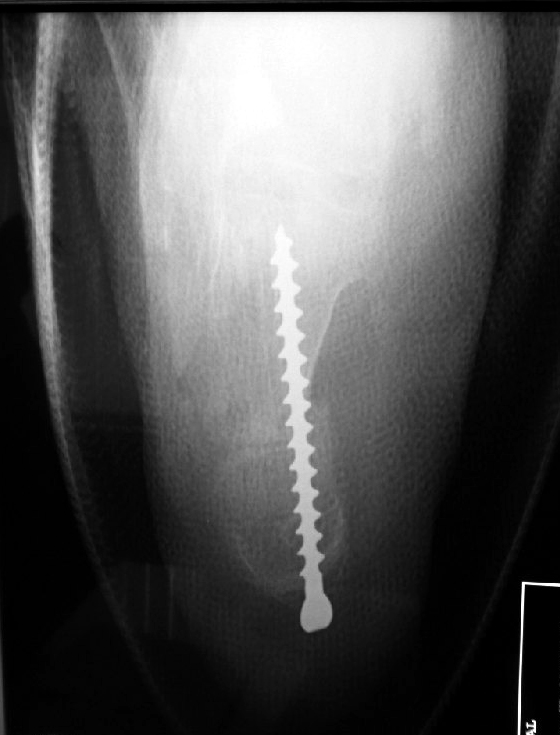

The guidewire is inserted to stabilise the cut heel bone temporarily while a screw is being inserted for final fixation.

Fluoroscopy in the operating room shows correct placement of a single fixation screw into the heel bone.